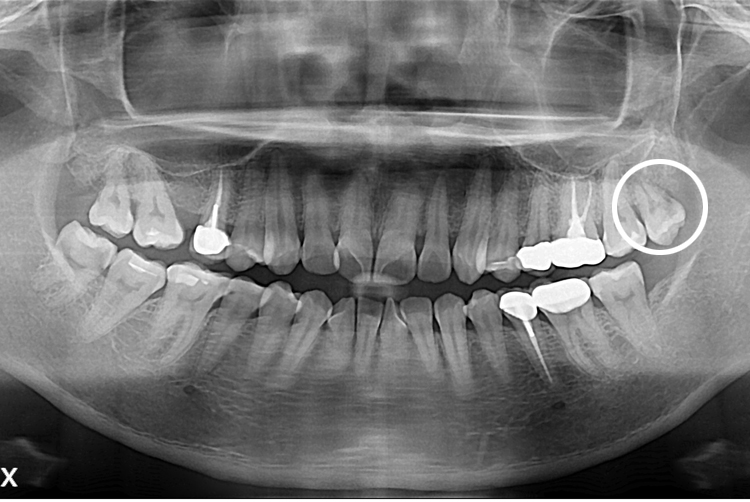

[사랑니] 단순매복 사랑니 발치

치료전 : 2020-11-18